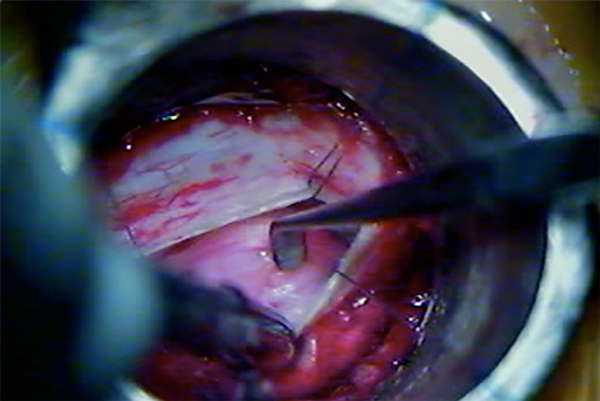

Cuando ya se encuentran en tracción los 4 puntos de reparo dural, los extremos de la incisión se aproximan entre sí, y eso permite incidir con bisturí dichos extremos para realizar una nueva tracción de los puntos de reparo, y así, una mayor exposición lateral (Fig. 7, 8 y 9).

Fig. 9: Exposición del contenido intradural mediante retracción dural percutánea.